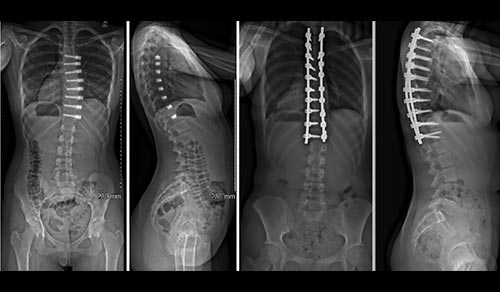

Our pediatric orthopedic specialists from Columbia are among the top in the country, offering specialized expertise in surgical and non-surgical treatments. Renowned for their expertise in congenital, neuromuscular, and traumatic disorders, clinicians and surgeons at the Children's Hospital of New York are also seasoned researchers, seeking to make surgeries safer while optimizing functional and mobility outcomes.

Pediatric Orthopedics